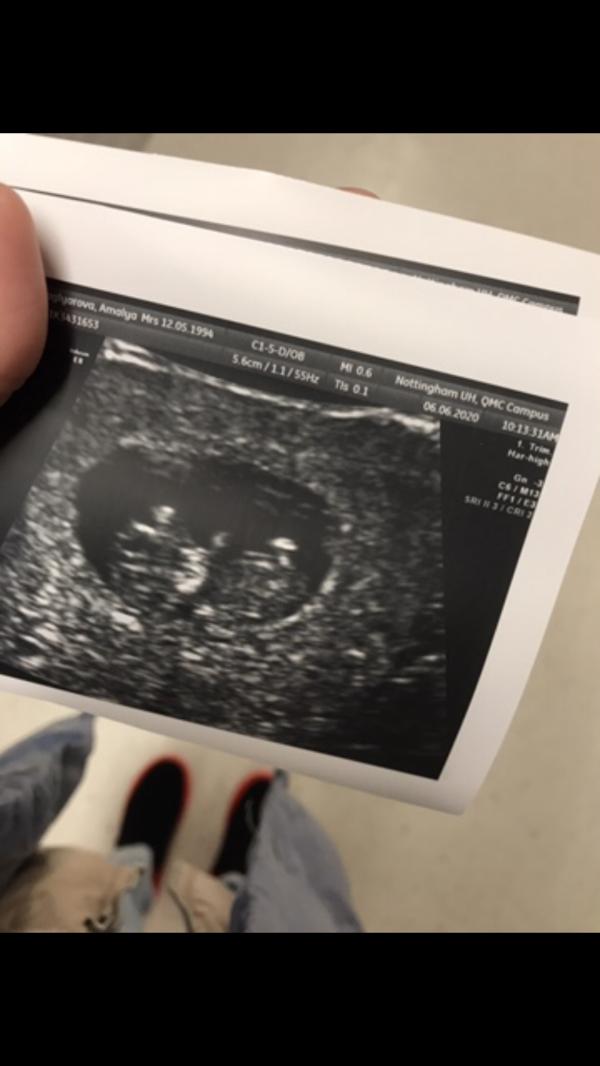

11 июня, на 12неделе я потеряла своего малыша😭 я видела его всего разочек... думаю об этом каждую секунду, незнаю как жить дальше... а жить надо.. ведь у меня сыночку 3года всего... я прокручиваю все моменты.. я просто в отчаянии...виню себя, врачей, которые знали про кровотечение, но ничем не помогли... все говорят, значит так должно было случиться, и ты бы ничего не смогла сделать, но мое сердце не может успокоиться и я схожу с ума просто....